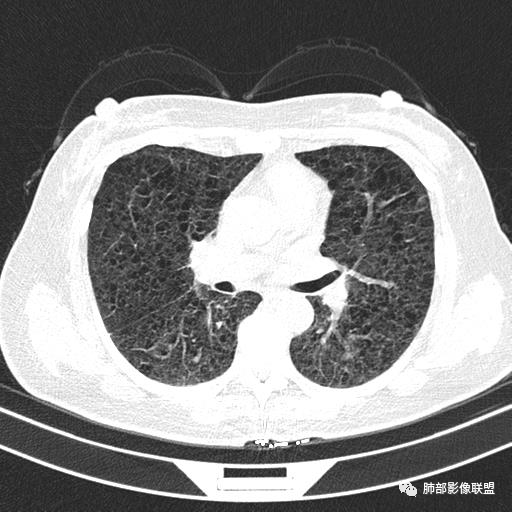

双肺弥漫囊腔,累及肋膈角,囊腔形态相对规则单一。

CT平扫示双肺弥漫分布大小不等囊状薄壁透光区,无内、中、外带分布差异,间质稍示增厚。拟LAM

中年女性育龄期妇女,咳嗽气喘,无吸烟史,有苯吸入史。影像:双肺弥漫均匀小囊腔,无明显分布优势,囊腔形态欠规则,壁薄,部分囊腔边缘血管征,伴双肺弥漫磨玻璃影,无结节,考虑lam,鉴别苯中毒肺损伤,囊腔多有分布优势,小叶中心分布为主,形态规整等

CT表现:双肺弥漫大小不等的薄壁囊腔,囊壁<2mm,外形规则,血管影多位于囊腔周围,囊腔之间肺组织正常,随着疾病进展到晚期,囊腔变大、增多,不可胜数,囊腔可融合成较大的囊,与肺气肿相似,形成间质性肺纤维化。部分病例可出现结节影。